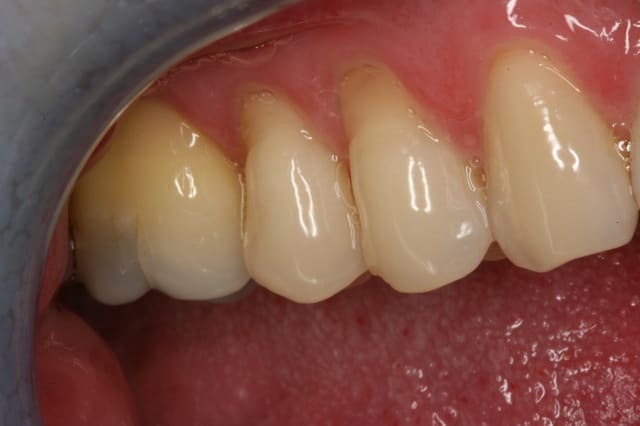

voici le post-op de la greffe d'il y a 2 semaines.

Je crois que je vais réduire l'épaisseur du greffon conjonctif... idéal 1,2mm?? est-ce exacte?la troisième étant la pré-op